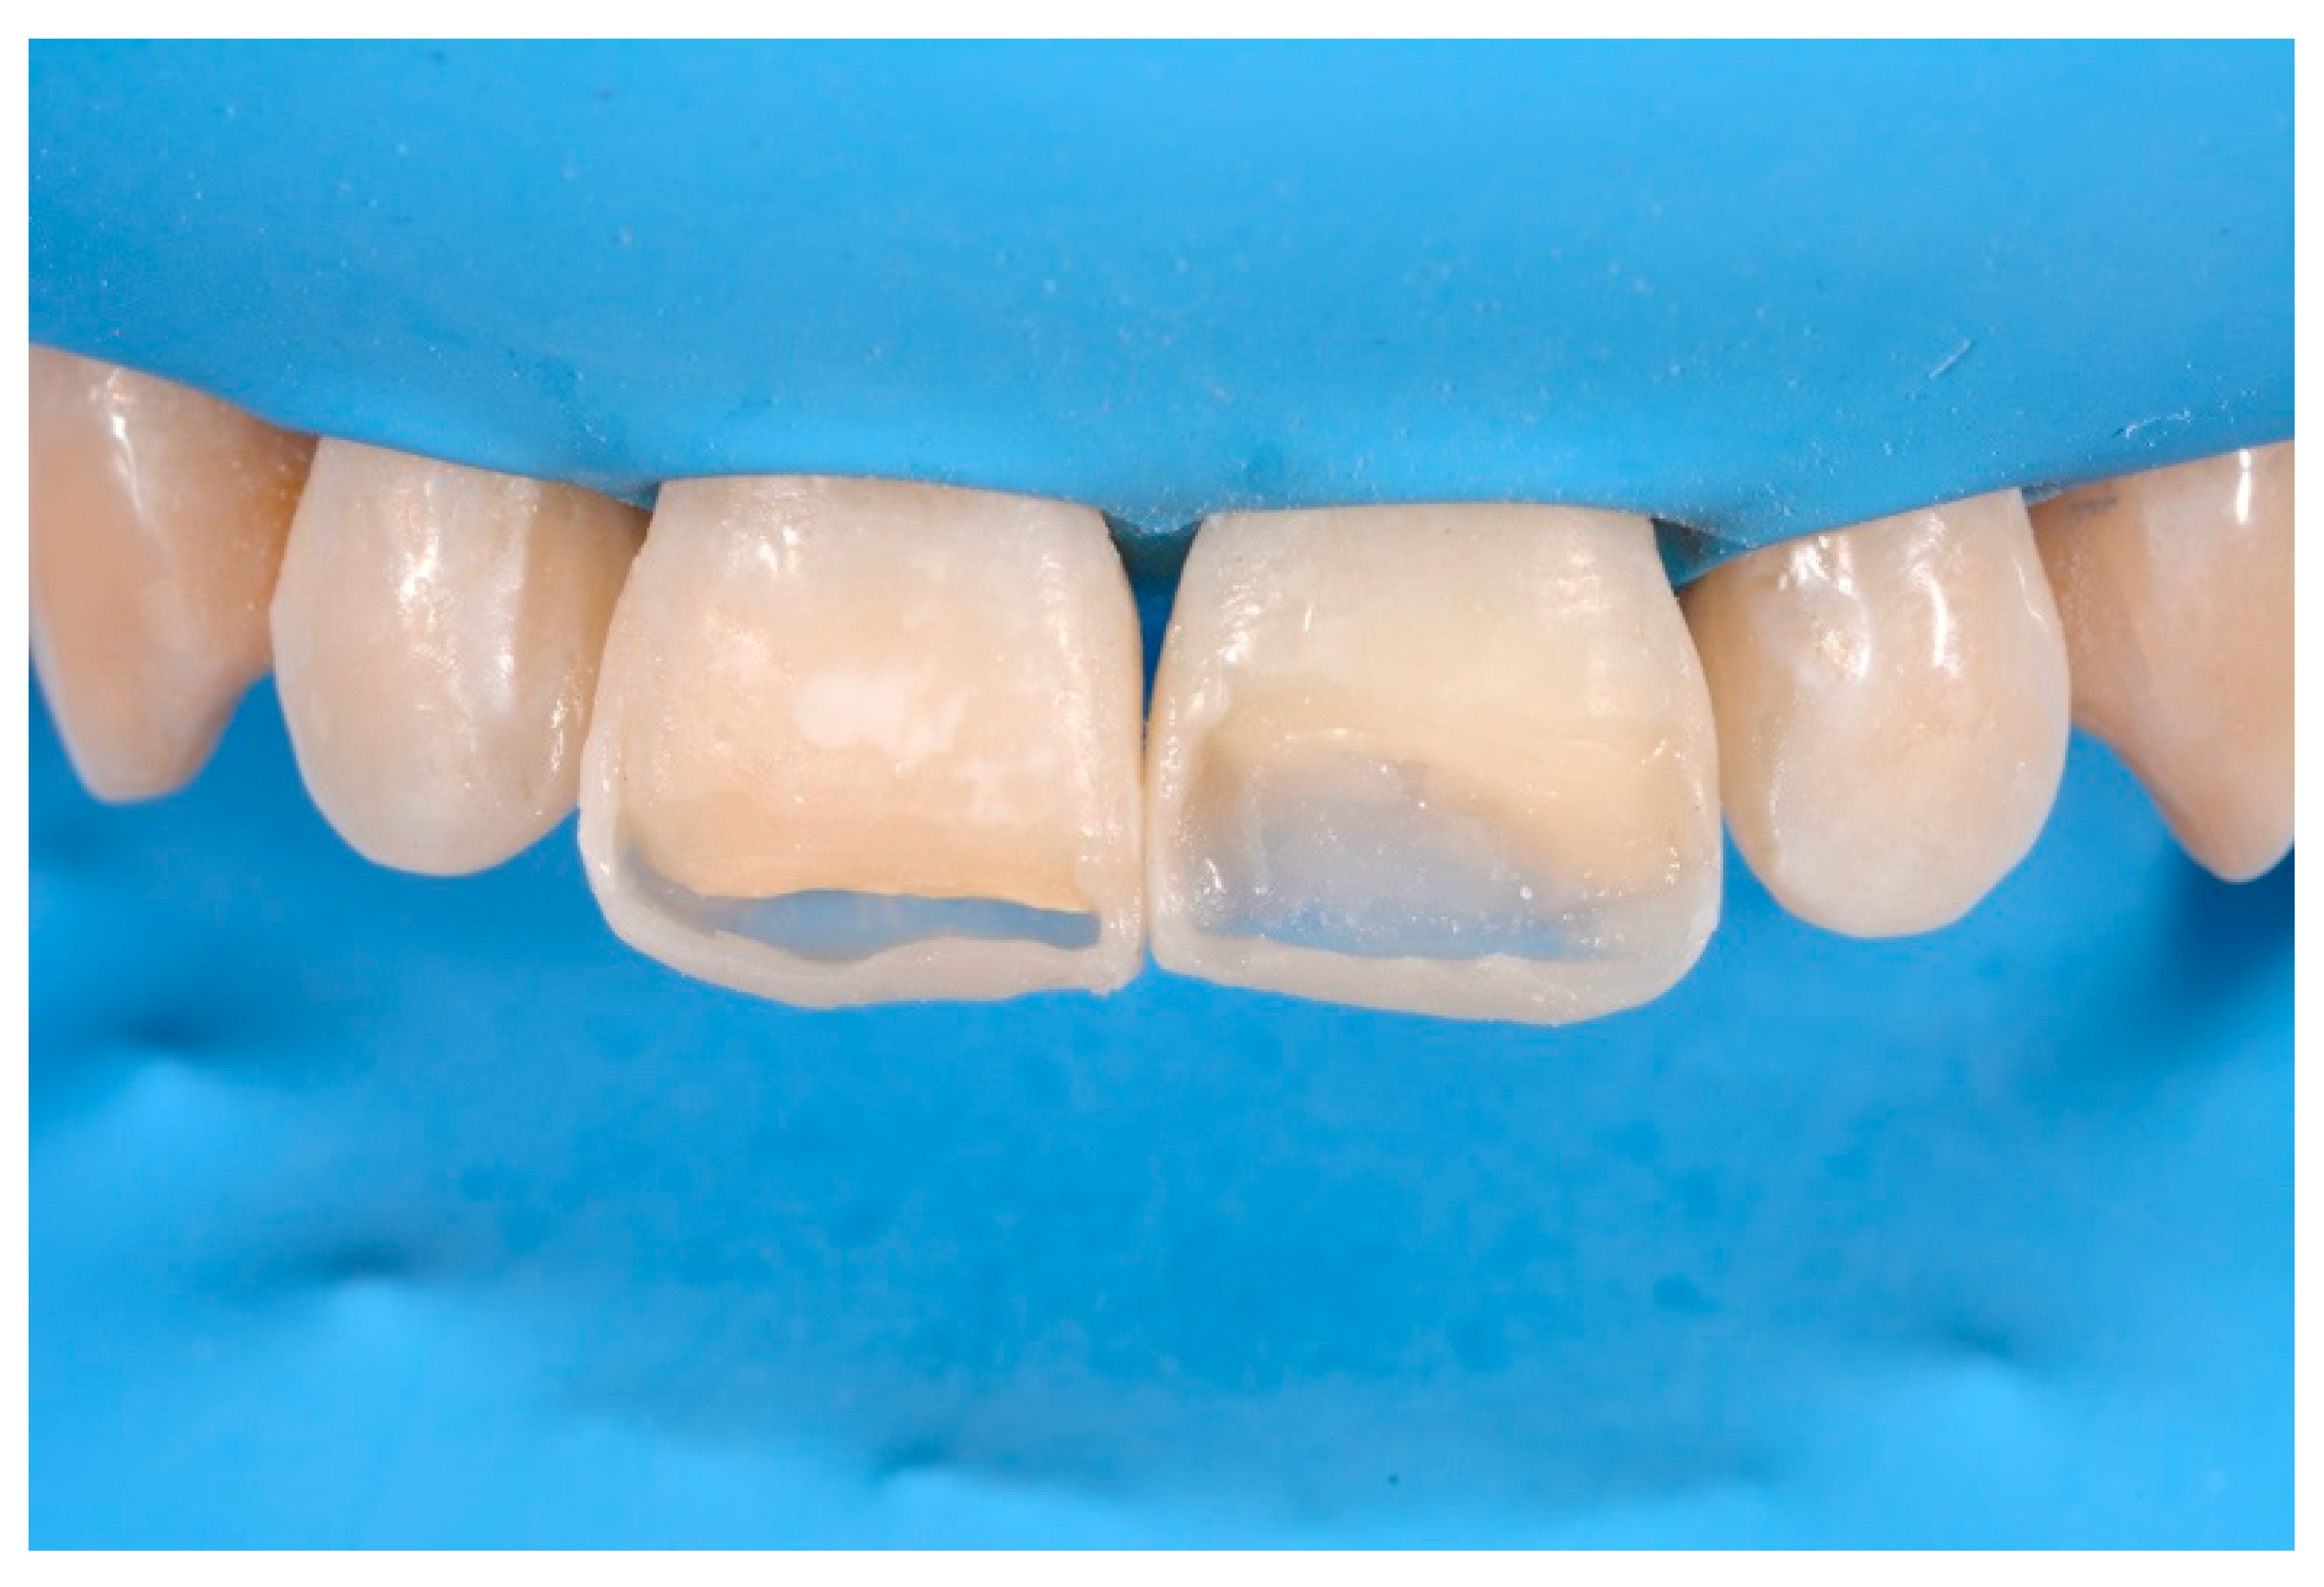

A 53-years old man presented to the dental office asking for the restoration of the mesial incisal angles of both central incisors (Figure 40). After preliminary shade analysis (using the button-try technique [14]) an attentive management of opaque and translucent shades was required to esthetically solve this case. After isolation with rubber dam, preparation, and adhesive procedures (Optibond FL, Kerr, Bioggio, Switzerland) the frame was completed using a translucent shade (Mosaic, ET, Ultradent Products, South Jordan, UT, USA) for palatal wall and an opaque material (Mosaic, A2, Ultradent Products, South Jordan, UT, USA) for incisal margin and interproximal walls. The external and internal excesses of the frame were modified (as described in Section 2.1.2) to obtain a uniform thin opaque outline as planned during the preliminary color/opacity analysis. This modification was performed to avoid the unfavorable uncovering of translucent areas during final finishing procedures that could result in an unaesthetic outcome. Once the definition of the external frame was completed, the mesial mamelon was modeled (Mosaic, A2, Ultradent Products, South Jordan, UT, USA) and the translucent material (Mosaic, ET, Ultradent Products, South Jordan, UT, USA) was applied. Finishing and polishing procedures (Jiffy, Ultradent Products, South Jordan, UT, USA) were completed afterwards.

Figure 40.